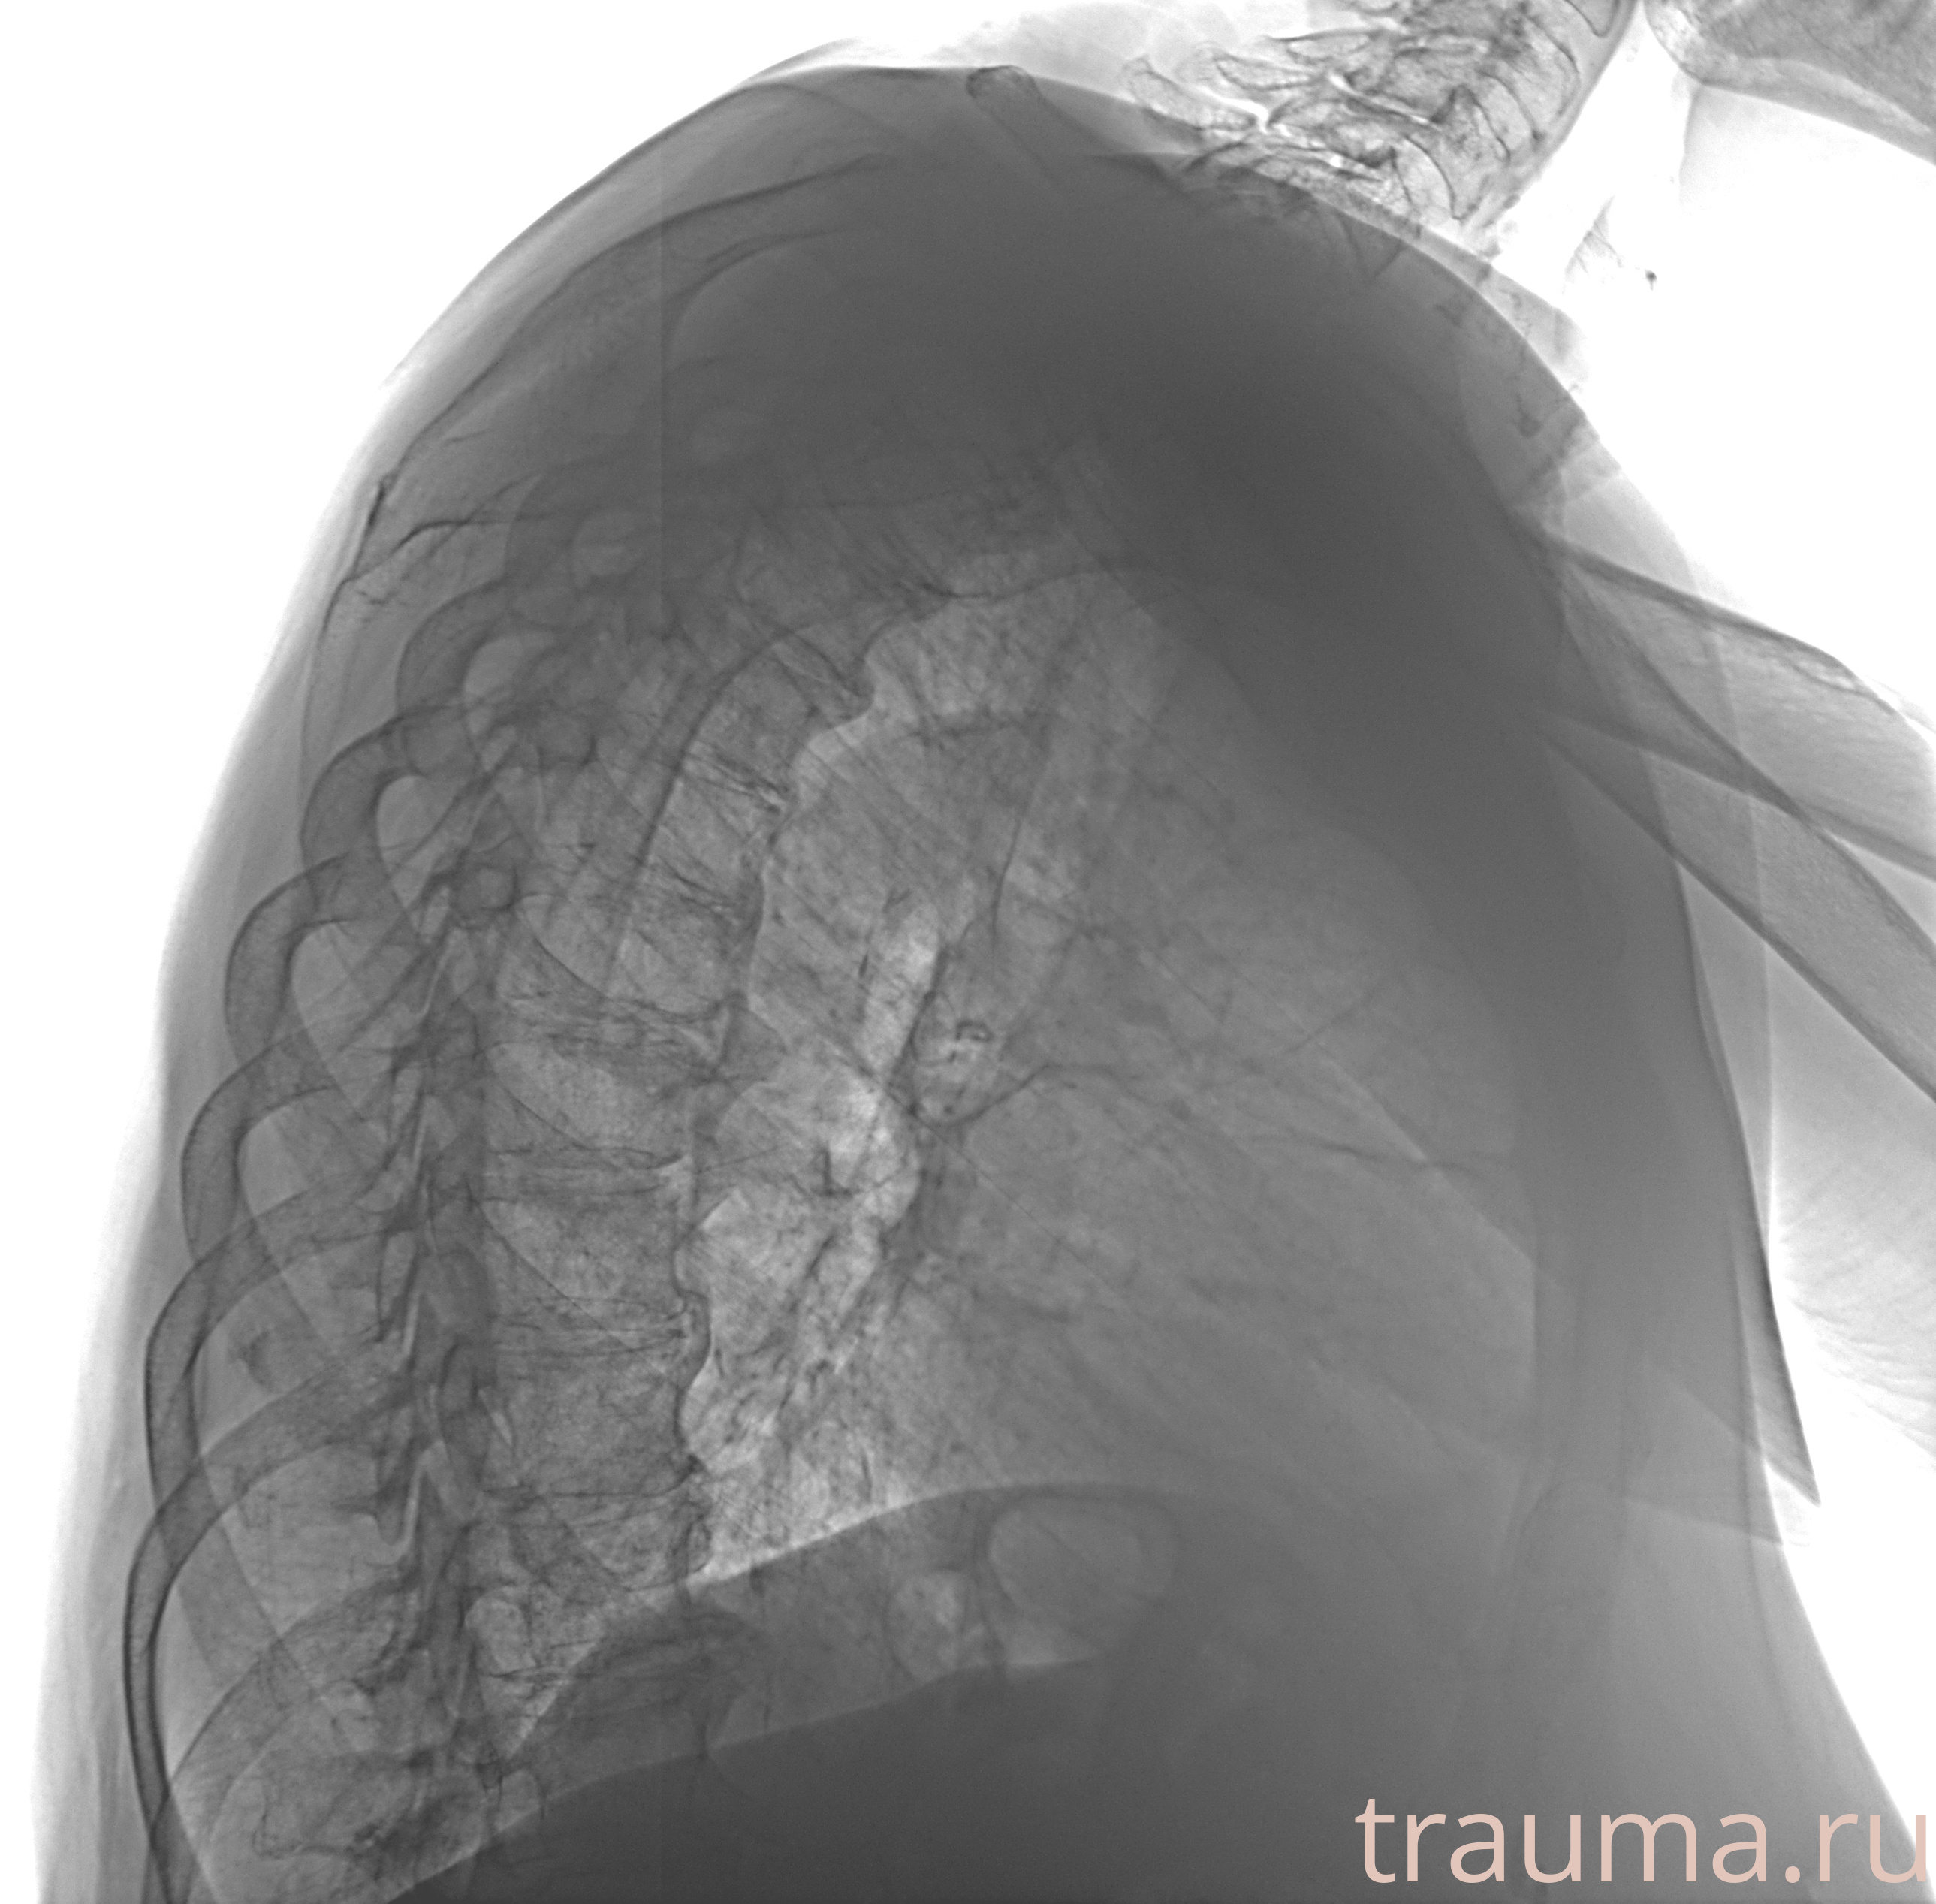

Рентген на дому: по вашему адресу приезжает врач-рентгенолог, травматолог-ортопед с мобильным рентгеновским аппаратом, проводит диагностику травмы или заболевания, делает необходимые рентгенограммы, дает рекомендации по дальнейшему лечению. Получить качественные снимки в домашних условиях возможно благодаря уникальной методике, разработанной МосРентген Центром для института  Склифосовского

при переломе шейки бедра и пневмонии от компании МосРентген Центр - партнера Института имени Склифосовского